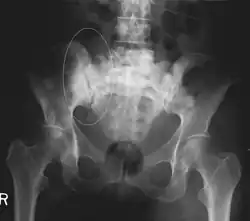

Sclerotic breast cancer metastases in the pelvis

CT scan in the coronal plane of bone metastases of the hip bone, in a 60-year-old woman with parotid gland cancer. The more affected side is very irregular and sclerotic (visible as brighter in this presentation).